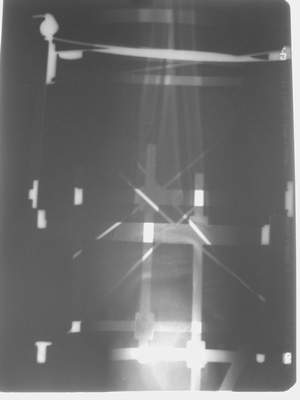

A> Это сросшийся перелом малоберцовой кости. И ложный сустав

A> н\3 б\берцовой кости.

Нашел в комп-ре схожий случай:

1) з/репозиция, 2) фиксация 2 спицами, 3) аппарат, 4) фиксационные

спицы удалены...

А можно было наложить аппарат и по поводу ложного сустава...

По крайней мере не было бы укорочения (пусть и в 2 см)...